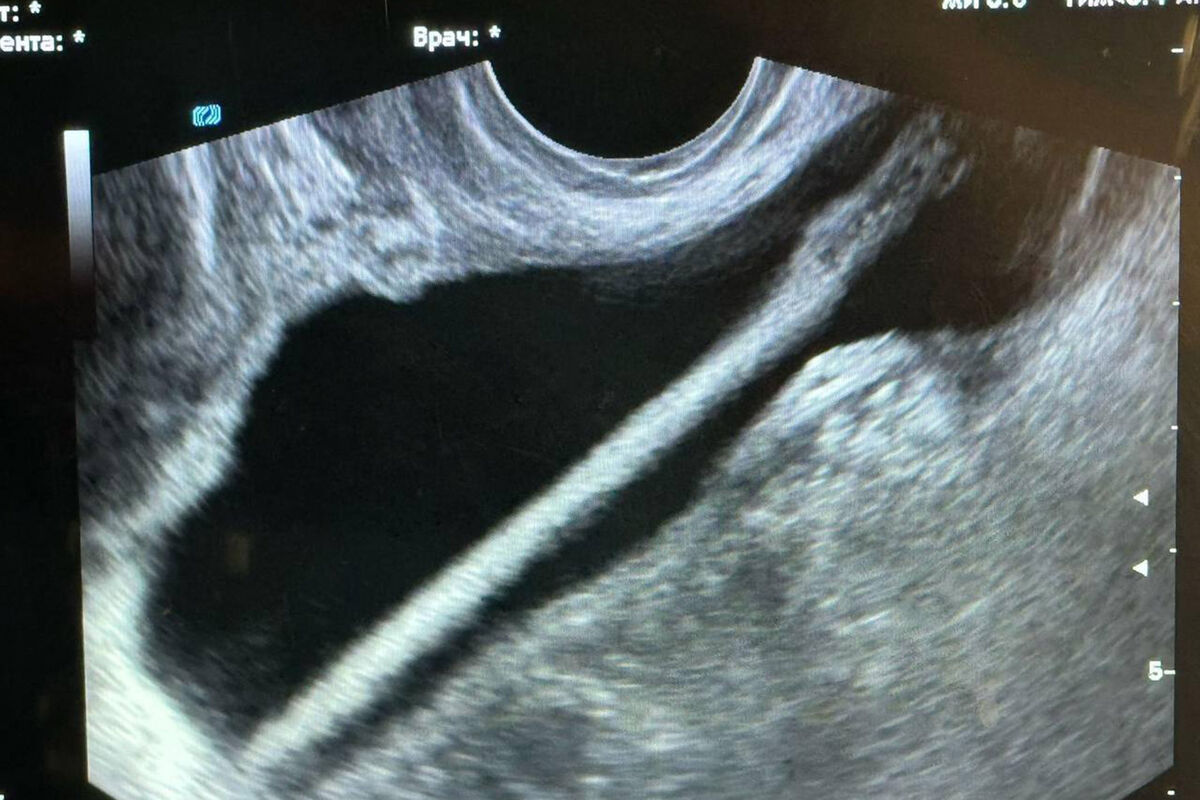

Инцидент произошел в Красногорской больнице. Пациентка обратилась в приемное отделение и рассказала, что ввела себе в мочевой пузырь через мочеиспускательный канал косметический карандаш. После обследования женщину госпитализировали в урологическое отделение.

С помощью эндоскопа хирурги извлекли инородное тело. Оперативное вмешательство прошло без осложнений, пациентку уже выписали домой. Однако медики предупредили, что подобные эксперименты могут привести к травмам, воспалениям и тяжелыми инфекциям.